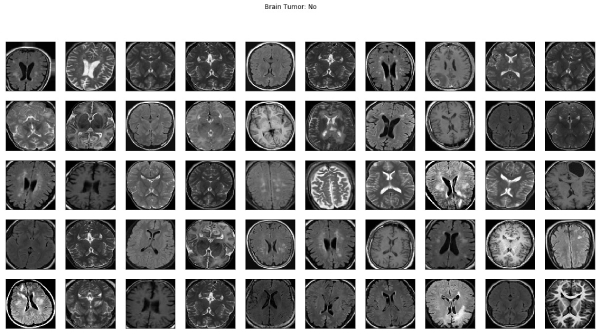

Brain Tumor Detection